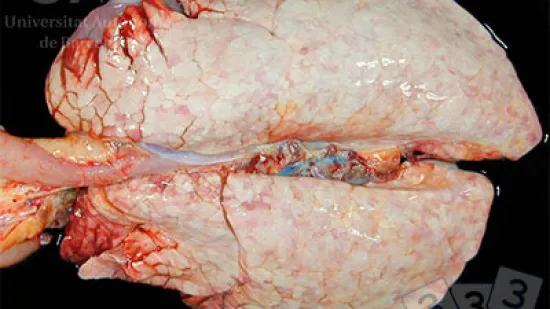

Semaine du 01-Nov-2021

Quelle est la cause de cette lésion pulmonaire ?